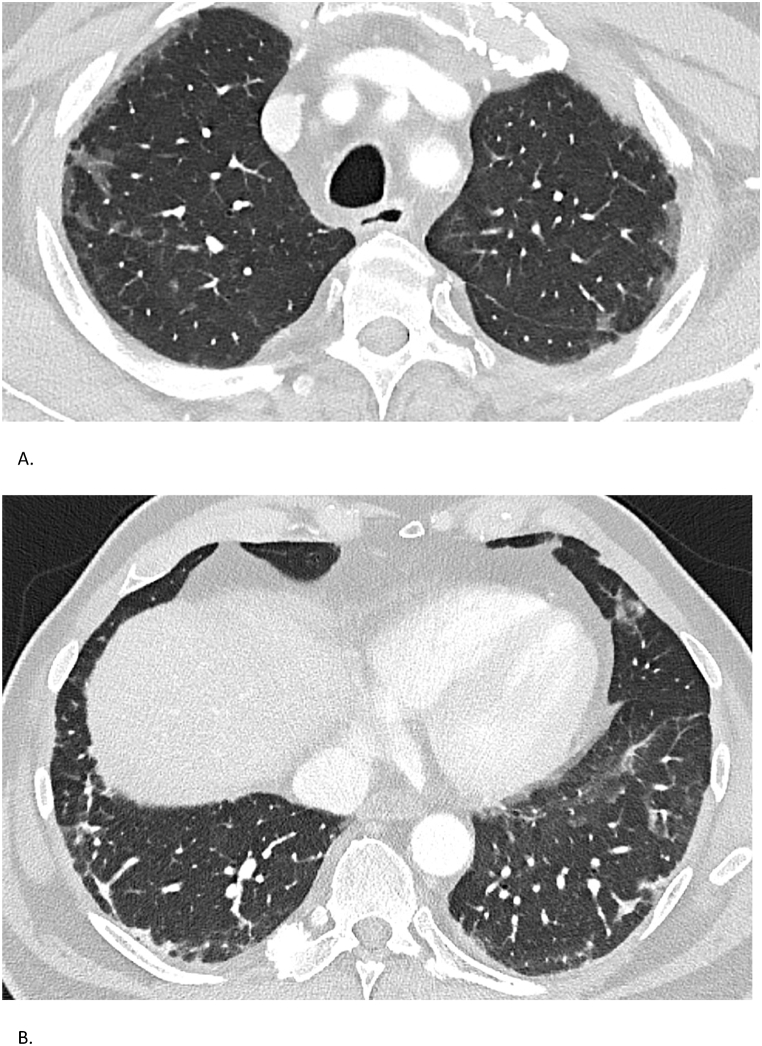

Fig. 3.

Case 3 – Chest CT findings

Serial chest CTs of a 69-year-old man with anti-MDA5-positive ILD. (A) CT on May 3, 2023, displays subpleural fibrosis and diffuse ground-glass opacities. (B) CT on the same date in a different plane confirms extensive fibrotic changes without honeycombing.

High-resolution chest CT demonstrated extensive subpleural fibrosis and ground-glass opacities, without honeycombing (Fig. 3). Lung function revealed a restrictive pattern with FVC of 2.73 L (68 %) and diffusing capacity (DLCO) of 69 % in April 2023. Anti-MDA5 IgG titers were initially 40 % and became undetectable on treatment by October 2023.